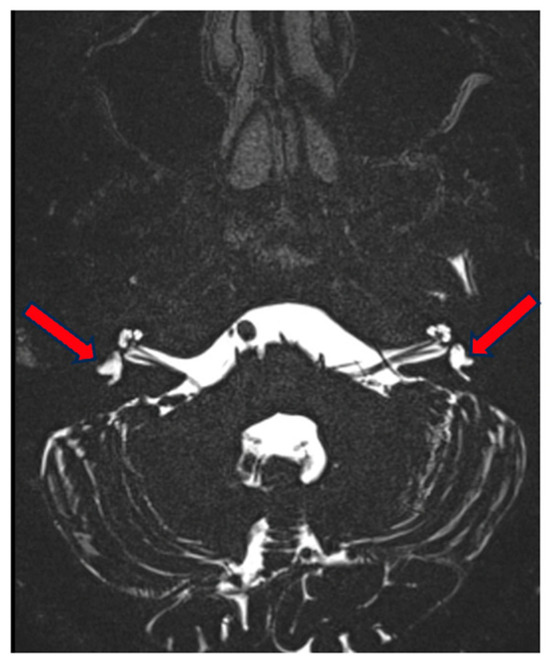

3.1. Case 1

3.2. Case 2

3.3. Case 3